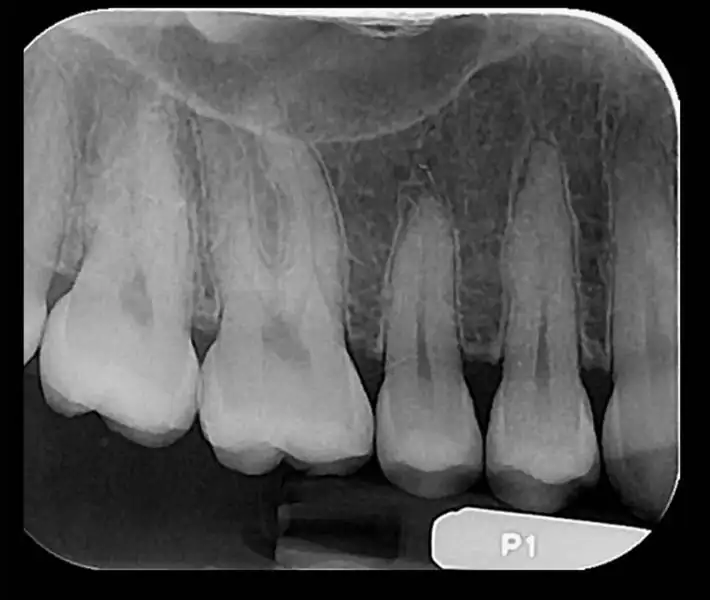

- رادیوگرافیهای داخل دهانی (پری اپیکال ،اکلوزال ،بایت وینگ)